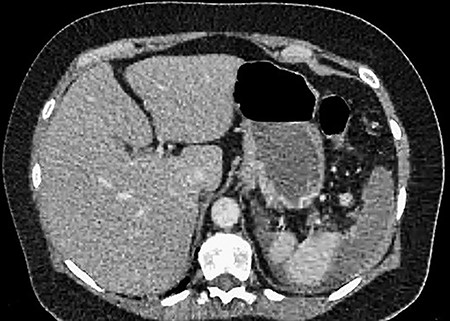

A 61-year-old female presented to a regional hospital with a 3-week history of intermittent diarrhoea, vomiting and generalized abdominal pain. She had a diffusely tender abdomen but was not peritonitic, and was shocked with a heart rate of 110 beats per minute, blood pressure of 89/45 mmHg and was peripherally cool. Her blood tests revealed a lactate of 7.2 mmol/L, which worsened to 7.8 mmol/L during resuscitation with intravenous fluids, and white cell count was 30.9 × 109/L, with an international normalized ratio (INR) of 1.4. She had an acute kidney injury with a creatinine of 119μmol/L and estimated glomerular filtration rate (eGFR) of 43 mL/min/1.73m2. Computed tomography (CT) revealed extensive thickened loops of non-enhancing small bowel with pneumatosis, moderate free fluid and a large splenic infarction. There was extensive thrombosis of the splenic vein and superior mesenteric vein extending into the portal vein to the level of the porta hepatis. Her background history included factor V Leiden and protein S deficiency, for which she had been non-compliant with warfarin during this illness. She had no surgical history (Figs. 1–5).

CT showing complete occlusion of the portal vein at the level of the porta hepatis.